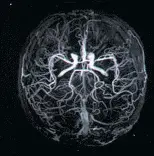

При проведенні МРТ на сучасному обладнанні видно навіть незначні зміни в мозку, пов’язані з порушенням мозкового кровотоку. Сучасне МРТ обладнання дозволяє бачити мінімальні зміни в ішемічному мозку, які тільки починають розвиваються на ранніх стадіях зниження кровотоку мозку.

Чітко видно інсульт (див. Нижче).